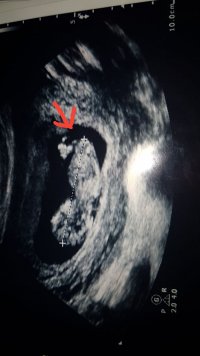

merhaba bu bebegimin 12 haftalik resmi doktor bu haftada erkek dedi suan 18 haftaligiz ve bir baska doktor 18 haftalikken ultrasonda bebek bagdas kurmus bacaklarini acmiyor kiz olabilir dedi simdi kafam karisti 12 haftalikken ki ultrason resmindeki bacak arasindaki cikinti ne anlama geliyor lutfen yorumlarmisiniz

merhaba bu bebegimin 12 haftalik resmi doktor bu haftada erkek dedi suan 18 haftaligiz ve bir baska doktor 18 haftalikken ultrasonda bebek bagdas kurmus bacaklarini acmiyor kiz olabilir dedi simdi kafam karisti 12 haftalikken ki ultrason resmindeki bacak arasindaki cikinti ne anlama geliyor lutfen yorumlarmisinizEkli dosyayı görüntüle 83671

aslinda merak ettigim su okla gosterdigim yer.12 haftalik bebegin genital organlari bu haftada tam olusmus olabilir mi ve ultrasonda bu kadar net gorulebilir mi ki doktorum cok net bir sekilde erkek demisti

Bebeğin cinsiyeti oluştuğu andan itibaren bellidir aslında ama bu en erken nub teoirisi ile 12. haftada öğrenilebilir. Bu haftalarda yanılma payı yüksektir bu nedenle benzer paylaşımların hepsine bebeğin cinsiyetinin 17-19-20 haftalarda net şekilde öğrenilebileceği notunu düşüyoruz.